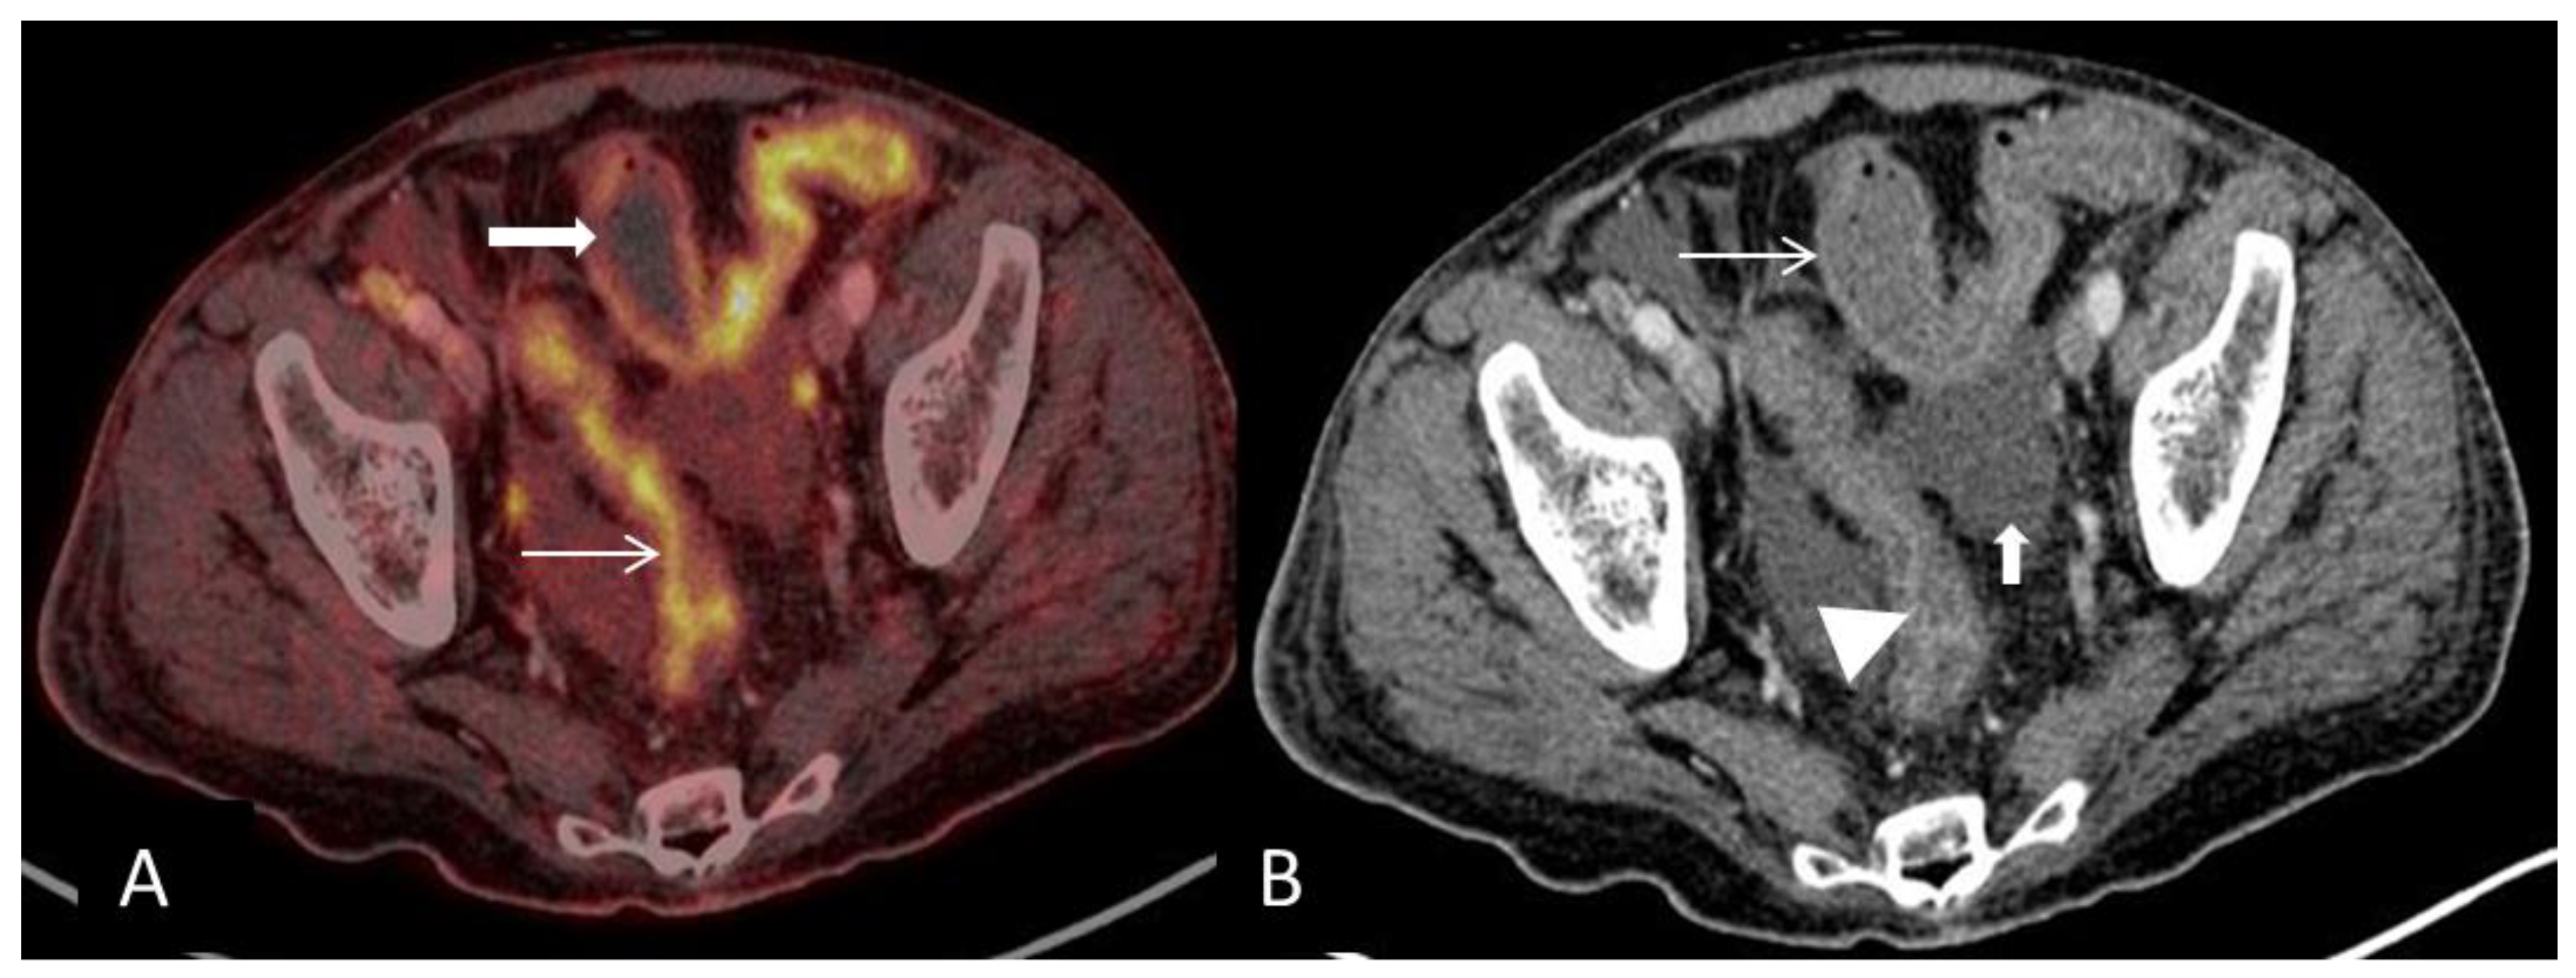

(A) Axial PET and CT fused image shows pathological high FDG-uptake in the large-bowel in two different patterns corresponding to the lumen (arrow) and in the outer wall (bold arrow) respectively and is consistent with an inflammatory response. (B) CT scan shows mural stratification (i.e., visualization of two or three different layers of the bowel wall) of the thickened large-bowel wall (defined as >3 mm) with mucosal (arrowhead) and serosal enhancement (arrow). The PET/CT findings described here are typical for acute GVHD-GIT or inflammatory bowel disease. Ascites is a common finding in acute-GVHD and has been reported to occur in 45% of affected patients (bold arrow) [2].